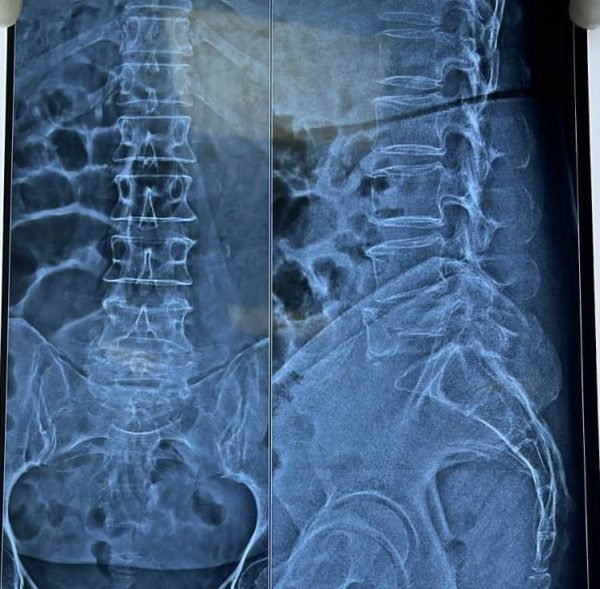

Posted on Nilesh KaduTrustindex verifies that the original source of the review is Google. I visited Dr. Nitish Agarwal for my severe back pain and shoulder issue. He checked my MRI very carefully and gave the perfect diagnosis. Yesterday, he performed the procedure (Root Block and Shoulder Injection), and it was completely painless. He is an expert and targeted the exact nerve point causing the trouble. Very helpful and humble doctor. Highly recommended for anyone with spine problems.Posted on Raju GorkhaTrustindex verifies that the original source of the review is Google. I was unable to make movement and suffered from right foot drop which is equal to halfway paralysis. Dr. Nitish Agarwal performed very fine microscopic surgery on L3, L4 & L5. After 90 days under his treatment I could go for a walk min. 6 kms a day, I have started my regular activities after 120 days. Thank you so much Dr. Nitish Agarwal sir.Posted on Pururaj GuravTrustindex verifies that the original source of the review is Google. I was suffering from severe back pain, and Dr. Nitish Agrawal has been extremely supportive throughout my treatment. He listened carefully, explained everything clearly, and guided me very well. His treatment has really helped me recover. He is one of the best spine specialists — highly recommended!Posted on Vinal AgrawalTrustindex verifies that the original source of the review is Google. I had consulted many doctors before Dr Nitish for my mother's spine issue,most recommended complex procedures and surgeries. Fortunately we found Dr Nitish and it has been life changing for my mother,she was in immense pain before the simple surgery he did. It's rare to find a surgeon who explains everything in detail and provides such exceptional care even after the surgery. I Would highly recommend him.Posted on Ajinkya MohadkarTrustindex verifies that the original source of the review is Google. My mother had sustained a fracture to her right hand wrist and we were worried about her recovery due to age factor. One of our family Doctor referred us to Dr. Nitish Agrawal and we visited Dr. Nitish Sir. Dr. Nitish sir ensured that my mother don't need a surgery and treated her by application of plaster (temporary and then cast-iron or Firm plaster) with certain orthopaedic treatment to hand and prescribed oral medication for ensuring recovery is faster without any surgery. Attaching the photo of xray which shows recovery of wrist bone which has rejoined and we are still continuing treatment to ensure my mother is fully recovered and is fit. Thank you Dr.Nitish Agrawal for your support.Posted on Samadhan LokhandeTrustindex verifies that the original source of the review is Google. Hi everyone, myself Samadhan. I was suffering from severe spine pain for a long time, and one of my friends suggested I visit Dr. Nitish Agarwal. Honestly, that was the best advice! Dr. Nitish listened to my problem very patiently, explained the cause in detail, and gave me the right treatment. I started feeling better within a short time. He is very polite, knowledgeable, and truly cares for his patients. I highly recommend Dr. Nitish Agarwal for anyone dealing with spine or back pain. Thank you, doctor, for your excellent treatment and support!Posted on POOJA JAGDALETrustindex verifies that the original source of the review is Google. Dr. Nitish Agrawal is an excellent spine specialist who patiently listens, explains the problem clearly, and provides the best treatment options.Posted on vipul pardeshiTrustindex verifies that the original source of the review is Google. Dr.Nitish sir is an incredible surgeon. I had excellent results from my recent spine surgery. The entire process, from consultation to recovery, was handled with professionalism and care. The outcome has been life-changing. I highly recommend Dr.Nitish agarwal to anyone in need of a spine surgeon.Posted on Deepak JadhavTrustindex verifies that the original source of the review is Google. A few months back I took treatment for my back pain from dr. Agarwal sir ...last 7-8 years i was suffering with low back pain,unbale to stand for more than 10 minutes..My low back hurts continuously, and also left leg pain was unbearable....i try every possible way of treatment from various suggestion...After several treatment...one of my relative suggested dr. Nitish Agarwal sirs name then I visited Dr. Nitish Agarwal sir in clinic. He suggested me x ray and MRI. On that basis he advise me caudal Block with root block with facet block for pain management. After block my pain goes with in a week. He advise me regular Physiotherapy at home. Now after regular exercise I am pain Free. Dr. Nitish Agarwal is a good doctor for any spine related problem.... Thank u dr. Agarwal Sir 🙏Posted on Kumar BTrustindex verifies that the original source of the review is Google. My wife had major infection in neck and lower back. She was bedridden. her legs and hands were weak. Then we admit her under Dr. Nitish Agarwal sir and did MRI. He explained that she is having major infection in cervical and lumbar spine. Due to infection her spinal cord is compressed so she was not able to walk. Then sir did operation for neck and removed infected tissue and spinal cord is freed and put a plate. Her lower back is treated with medicine only. She was given 2 months antibiotics by saline and 5 months oral antibiotics were given. He also advised regular exercise. After 15 days of surgery she started walking with support. Now after 1 year she is completely alright and walking like a normal person. She is regularly doing all her activities. Now she can also travel by 2 wheeler. Thank you to Dr. Nitish Agarwal sir for his expert work in spine. I recommend Dr. Nitish Agarwal for any spine related problem.